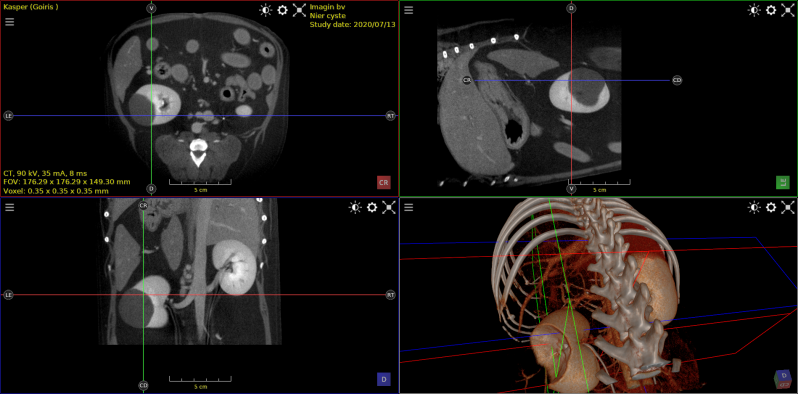

Hond met nier cyste en hernia in de lendenwervel. Schmörsle nodule in het wervel lichaam